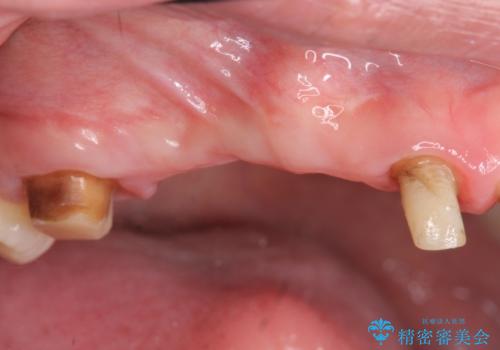

虫歯による多数歯欠損 インプラント咬合機能回復

- 虫歯が多発し、多数失ってしまった歯の審美性回復・機能回復を計画します。

多数の歯が失われておりブリッジは行えないような状況で、インプラント治療か入れ歯治療かを提案しインプラント治療を希望・選択されました。